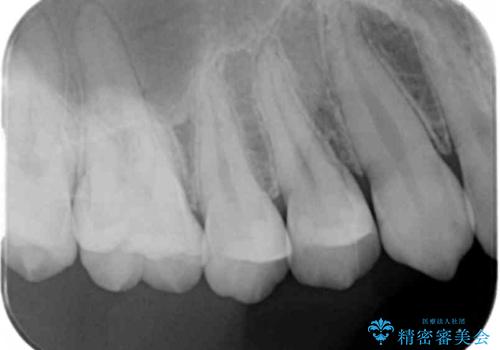

- 検査の結果奥歯と奥歯の間に虫歯が確認されました。

虫歯を取り除いた後、セラミックインレーで修復していきます。

- 右上45 セラミックインレー 77,000円×2本費用は治療当時の料金となります

外からは確認しにくくても中で大きく虫歯が広がっていることはよくあります。